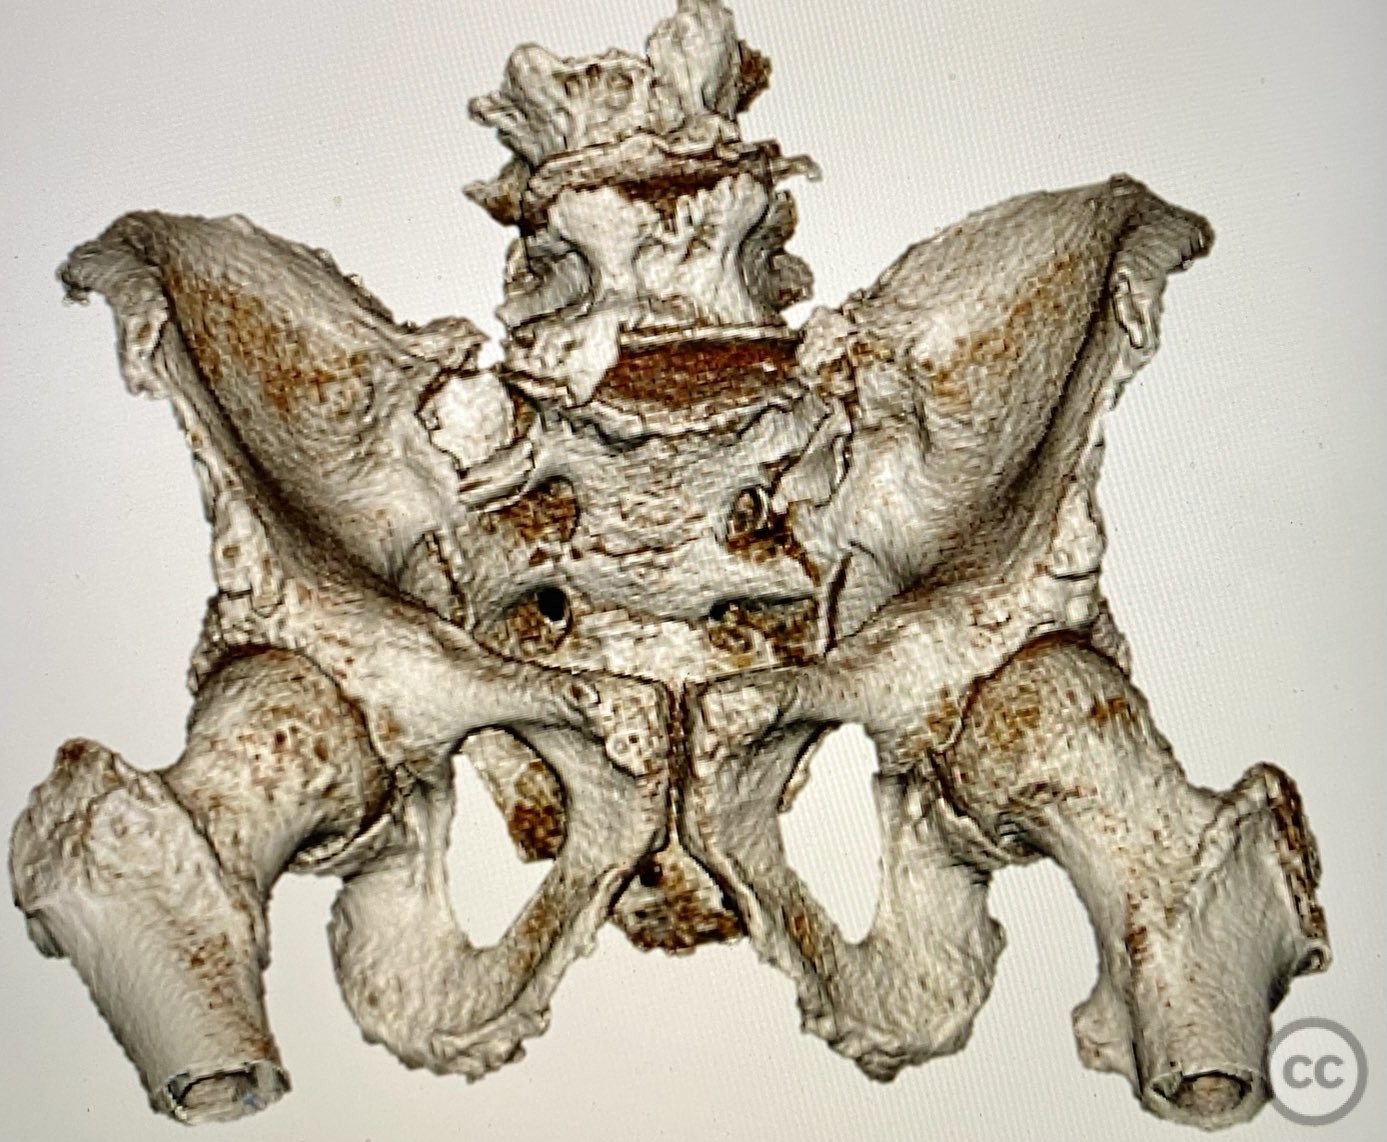

Clinical and radiological findings:  An elderly patient presented with a complex upper sacral fracture characterized by oblique fracture pathways bilaterally, described as a "UYH+pattern" fracture. The patient exhibited compromised bone quality consistent with age-related osteopenia or osteoporosis. Initial clinical assessment prioritized pain control and early mobilization. Radiological evaluation, including computed tomography (CT), confirmed the oblique orientation of the upper sacral fracture lines and their bilateral extension. No neurovascular compromise was reported.

Planning remarks:  The preoperative plan involved percutaneous stabilization of the bilateral oblique upper sacral fractures using a cannulated, articulated intramedullary fixation device (CurvaFix). The anatomical approach was planned to accommodate the oblique trajectory of the sacral fracture pathways, with bilateral guide pin placement under fluoroscopic guidance, followed by device insertion and locking.

The articulated nature of the CurvaFix device allowed precise accommodation of the complex oblique upper sacral fracture pathways bilaterally. Percutaneous technique minimized soft tissue disruption and surgical morbidity. Postoperative CT imaging confirmed satisfactory device placement and fracture reduction. The achieved stability provided immediate pain relief, reduced or eliminated narcotic requirements, and enabled early mobilization. Surgeons with experience in device removal have reported no technical difficulties.